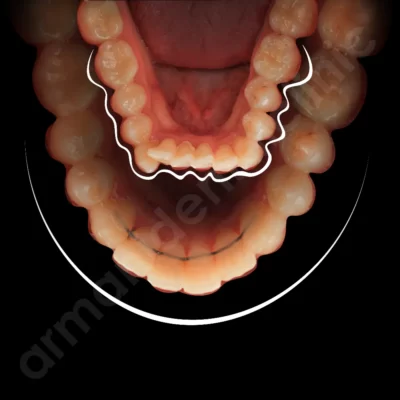

مراقبتهای حین درمان ارتودنسی نقش اصلی را در موفقیت و سرعت رسیدن به نتیجه نهایی دارند. در این دوره دندانها در حال حرکت و جابهجایی هستند و هرگونه بیتوجهی میتواند باعث کند شدن روند درمان، آسیب به براکتها یا حتی نیاز به شروع مجدد مراحل شود.

رعایت اصول بهداشت دهان، پرهیز از خوردنیهای آسیبزا و حضور منظم در جلسات تنظیم، باعث میشود دندانها بدون مشکل در مسیر درست حرکت کنند و مشکلاتی مثل پوسیدگی، التهاب لثه یا شکستن براکتها به حداقل برسند.

همچنین مراقبت مناسب در طول درمان از بروز لکههای سفید، پوسیدگی دندان، بوی بد دهان یا آسیب به لثهها جلوگیری میکند. اگر بیمار در این دوره همکاری نکند. مثل شکستن مکرر براکتها، از دست دادن کشها یا عدم رعایت رژیم غذایی—مدت درمان طولانیتر شده و احتمال باقی ماندن مشکلات پس از پایان ارتودنسی افزایش پیدا میکند. به همین دلیل، پایبندی دقیق به توصیههای متخصص، مهمترین عامل در رسیدن به لبخند ایدهآل است.